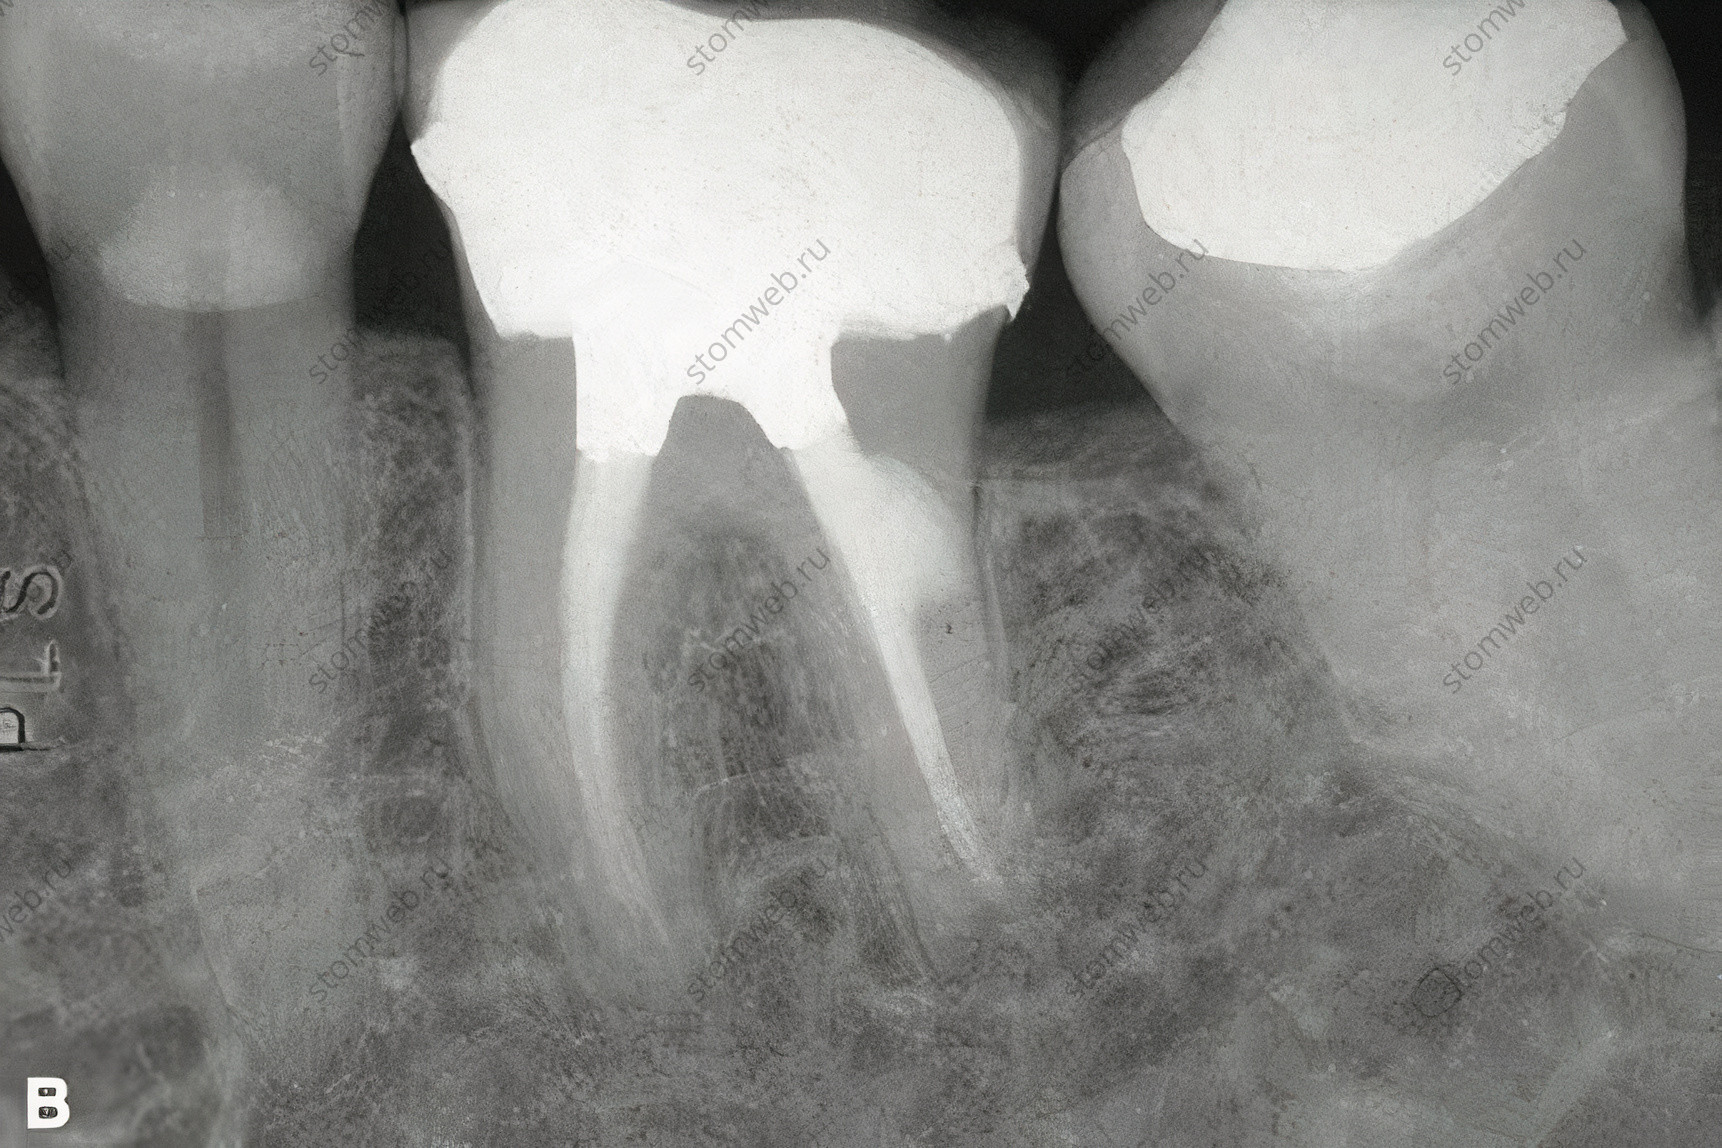

Одно патологическое состояние, к которому может привести трещина коронки и которое можно увидеть на снимке - внутреннюю резорбцию из-за воспаления пульпы, вызванного бактериями (Рис. 18). Этот вид внутренней резорбции уникален, он примыкает к пульповой камере, и его часто путают с инвазивной внешней резорбцией. Наличие трещины, связанной с резорбцией, и отсутствие сообщения дефекта с тканями пародонта подтверждает диагноз.

Рисунок 18. Иллюстрация внутренней резорбции, связанной с трещиной. А. Симптоматичная трещина, расположенная на дистальный поверхности нижнечелюстного моляра. На снимке показана локализация резорбции (указано стрелками). В. Снимок после эндодонтического лечения и покрытия коронкой. Резорбция имела сообщение с витальной пульпой в том месте, где трещина входила в полость пульпы; внешнего сообщения не было.